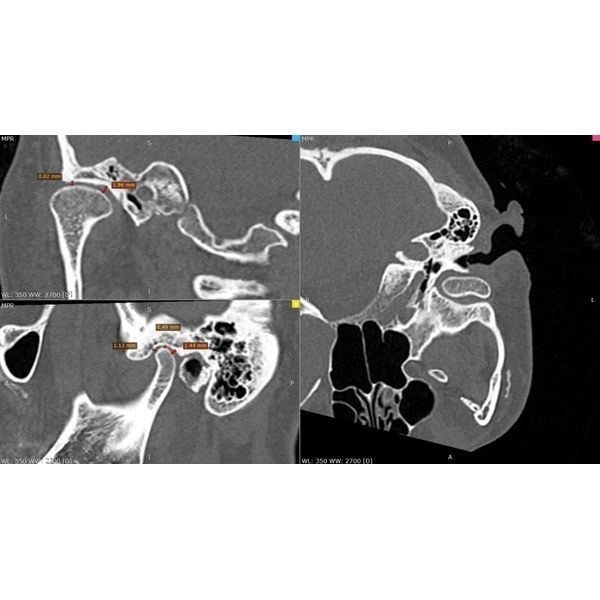

Конусно-лучевая компьютерная томография (КЛКТ) показала:

- очаги разрушения костной ткани в области корней зубов 2.7 и 1.7 — кисты, периодонтит;

- почти идеальное строение левого сустава — суставная головка округлая, с чёткими границами, но суставная щель заметно меньше нормы, т. е. челюсть смещена назад и вверх;

- изменения в правом суставе — деформация суставной головки в сочетании с узурами (эрозиями), участок перестройки костной ткани с «клювовидным» выступом, смещение головки назад;

- однородное заполнение большинства корневых каналов рентгеноконтрастным материалом.